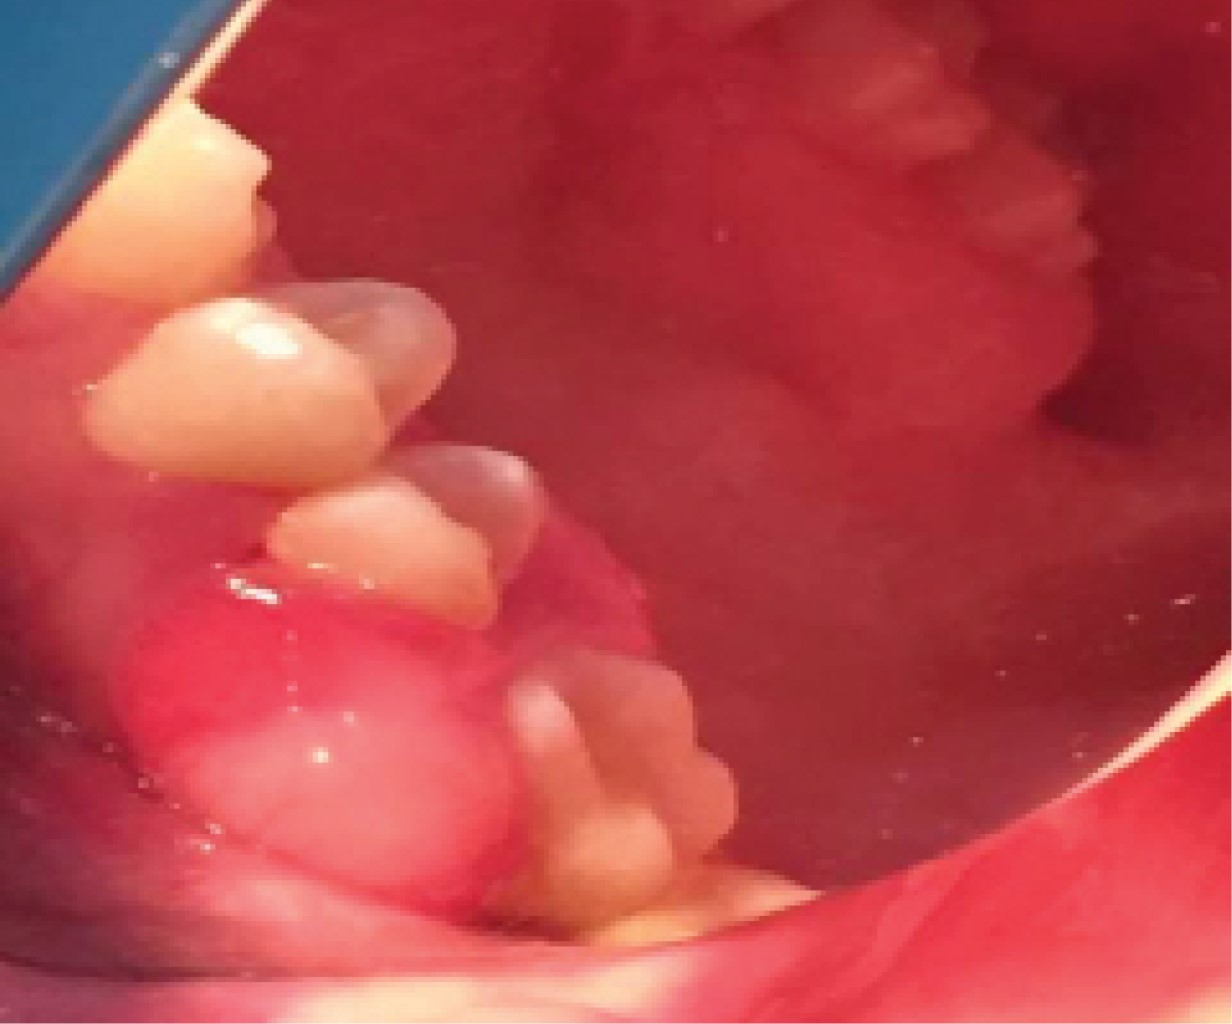

Figure 2